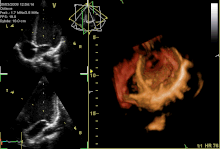

Several imaging methods can be used to assess the anatomy and function of the heart, including ultrasound (echocardiography), angiography, CT scans, MRI and PET. An echocardiogram is an ultrasound of the heart used to measure the heart's function, assess for valve disease, and look for any abnormalities. Echocardiography can be conducted by a probe on the chest ("transthoracic") or by a probe in the esophagus ("transoesophageal"). A typical echocardiography report will include information about the width of the valves noting any stenosis, whether there is any backflow of blood (regurgitation) and information about the blood volumes at the end of systole and diastole, including an ejection fraction, which describes how much blood is ejected from the left and right ventricles after systole. Ejection fraction can then be obtained by dividing the volume ejected by the heart (stroke volume) by the volume of the filled heart (end-diastolic volume).[77] Echocardiograms can also be conducted under circumstances when the body is more stressed, in order to examine for signs of lack of blood supply. This cardiac stress test involves either direct exercise, or where this is not possible, injection of a drug such as dobutamine.[69]